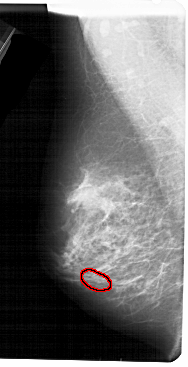

A_1506_1.LEFT_MLO

FILE: A_1506_1.LEFT_MLO.OVERLAY

TOTAL_ABNORMALITIES 1

ABNORMALITY 1

LESION_TYPE CALCIFICATION TYPE PLEOMORPHIC DISTRIBUTION CLUSTERED

ASSESSMENT 4

SUBTLETY 2

PATHOLOGY MALIGNANT